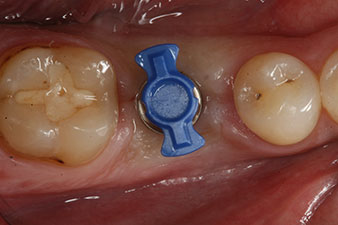

The implant was placed as planned after thorough removal of the granulation tissue (blueSky, bredent).

The torque used for the machine-driven placement was 43 Ncm. In addition, after screwing a measuring post (SmartPeg) specially matched to the implant, the ISQ value was measured with the probe of the W&H Osstell ISQ module.

This module is an optional extra for the W&H Implantmed and is docked to the implantology motor (see Fig. 11). The dimensionless ISQ value immediately after insertion was 64 orovestibular and 68 mesiodistal (maximum value = 100).

These values could have indicated open healing or even immediate restoration. Due to the insufficient crestal bone volume at the implant, the region was augmented with the bone chips collected during preparation of the implant bed and sutured to exclude saliva.